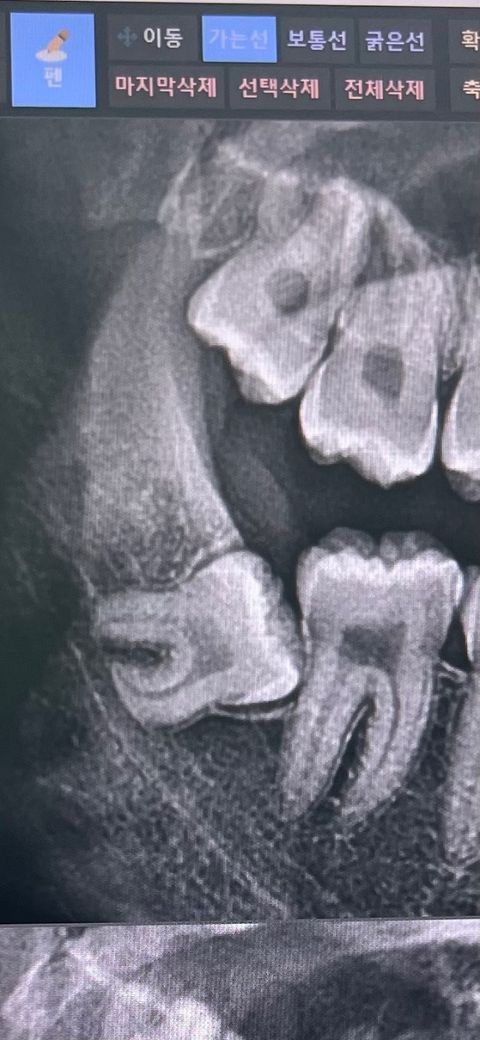

매복사랑니 이정도면 심각한건가요.

매복 사랑니 이정도면 심각한건거요 뽑기힘든 사랑니인가요 . ………………………………………………………………………..

매복깊이가 깊어서 사랑나 발치시 난이도가 상당할것으로 예상됩니다. 사랑니 전문 병원에 가셔서 발치를 하시는게 좋을것같습니다.

발치 난이도 높을 것 같습니다. 아래턱 신경관과 거리가 가깝고, 치아 뿌리가 굽어있고, 뿌리 자체도 튼실하고, 옆 어금니와 겹치는 부분도 있네요

사진으로 봤을 경우에는 매복된 깊이가 깊어 보입니다. 매복된 사랑니의 경우에 맹출되어 있지 않으면 주변 조직에 문제를 발생시키지 않기 때문에 발치를 하지 않아도 됩니다. 발치를 하고자 한다면 난이도가 높은 발치일 것으로 생각됩니다.